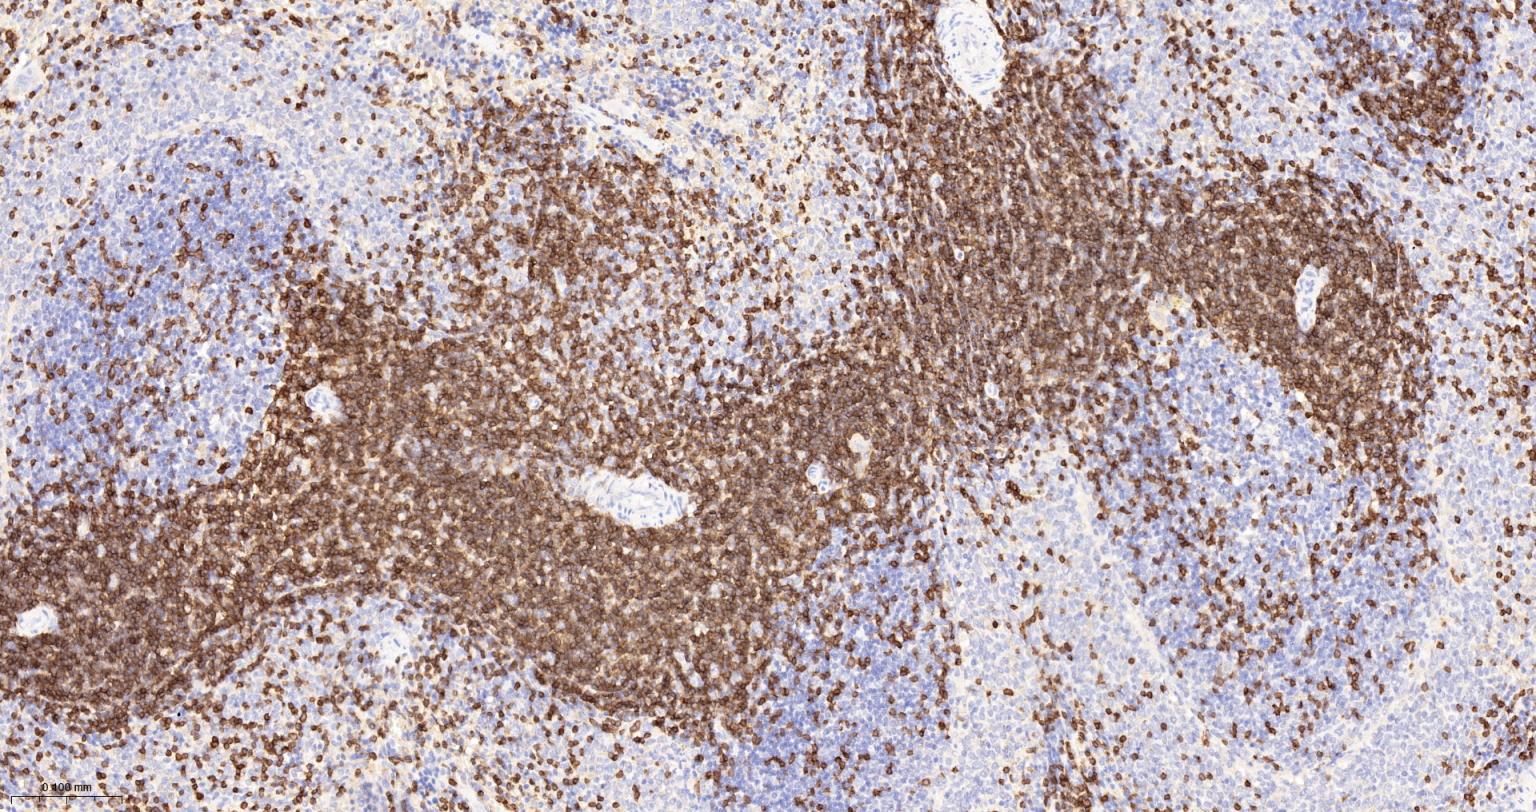

IHC-PHuman, Mouse, Rat1:500-2000

IHC-FHuman, Mouse, Rat1:500-2000